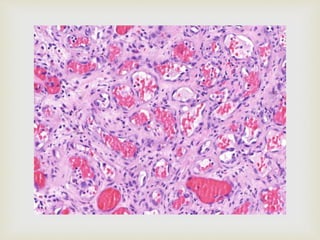

 Cavernous hemangioma

 Large dilated blood sinuses with thin walls showing

endothelial cells

 Sinusoidal spaces are usually filled with blood

 Sometimes lymph vessels may be present

HEMANGIOMA